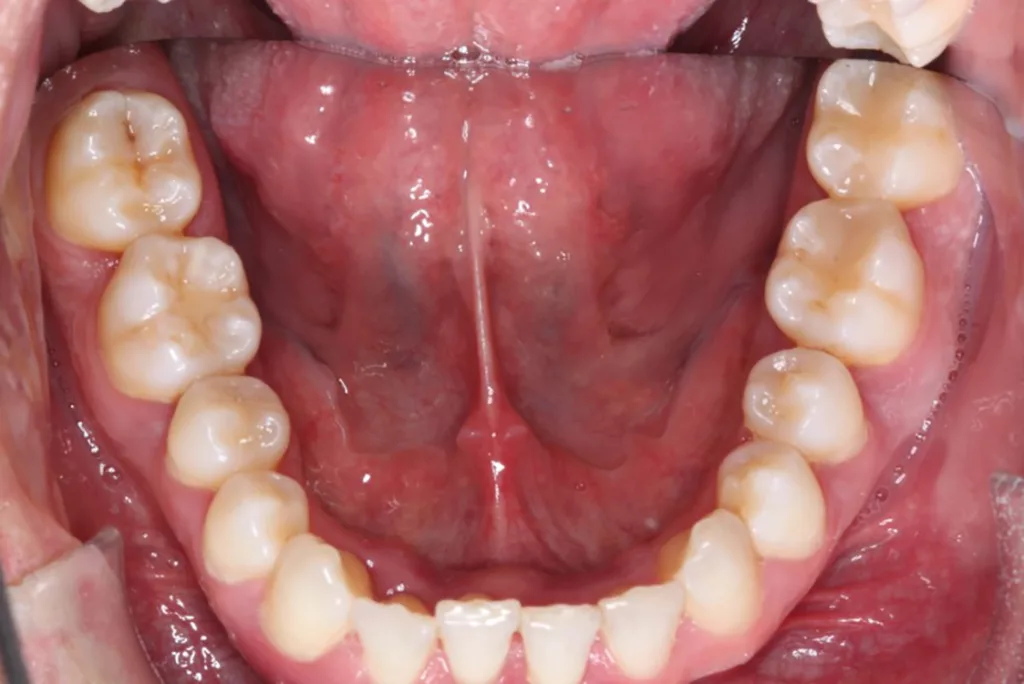

Robuste Evidenz aus aktuellen großen bevölkerungsbasierten Studien zeigt eine Überlegenheit der Effektivität elektrischer Zahnbürsten gegenüber Handzahnbürsten. Darüber hinaus legen systematische Übersichtsarbeiten und In-vitro-Studien einen zusätzlichen Effekt – die Putzwirkung auch ohne direkten Borstenkontakt durch unterschiedliche Strömungsphänomene – bestimmter elektrischer Zahnbürsten (Schallzahnbürsten) nahe. Laboruntersuchungen zeigen aber auch große Unterschiede der untersuchten Zahnbürsten hinsichtlich der Effektivität der Biofilmreduktion. Das bedeutet, dass in der Klinik (Abb. 7–9) in aller Regel eine Empfehlung für elektrische Zahnbürsten und (!) geeignete Hilfsmittel für die Zahnzwischenraumpflege vorliegen sollte.